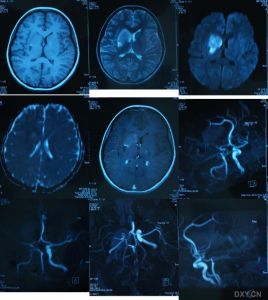

主要表現為頭痛、嘔吐、視乳頭水腫、癱瘓、部分性運動性癲癇發作等,常伴不同程度的意識障礙。這些雖然擬似顱內占位病變的症狀,但起病急,病情迅速加重,從起病至症狀頂點短者僅數小時,多數均在一個月內;顱內壓急劇增高,部分患者可迅速出現顱內壓增高危象;頭顱CT和MRI檢查均可見彌散性腦水腫和腦軟化區等,均有助與腦瘤鑑別,但確診有時需依賴開顱探查或立體定向鑽孔穿刺進行腦組織活檢。

患者病前無癲癇史。常見的發作類型有全身性強直陣攣發作及其連續狀態,部分性運動發作、複合性部分性發作或混合性發作。本型患者起病後均以癲癇發作為主要症狀,有些患者在癲癇發作前可有發熱、頭痛、頭昏、嘔吐、主動活動減少等前驅症狀,隨後出現彌散性異常,腦脊液檢查輕度異常或正常,CT及MRI可見彌散性腦水腫,單個或多個灶性病變等,為症狀性癲癇的診斷提供了依據;散發性腦炎的其它表現有助本病的臨床診斷。

以偏癱、單癱、交叉性癱、四肢癱、運動性共濟失調、錐體外系不自主運動、顱神經損害為主要臨床表現,表明病變位於大腦的某一局部,或位於小腦或腦幹。根據起病緩急、疾病發展過程、腦脊液檢查、CT或MRI以及對試驗治療的反應與腦血管病、腦瘤、多發性硬化症鑑別。

4、顱腦CT可見腦內大小不等、邊界不清的低密度灶。

5、放射學檢查:常規頭顱放射學檢查對散發性腦炎的診斷無重要價值。頭顱CT有時可見大腦半球多個散在的軟化灶,對排除占位性病變有一定意義。